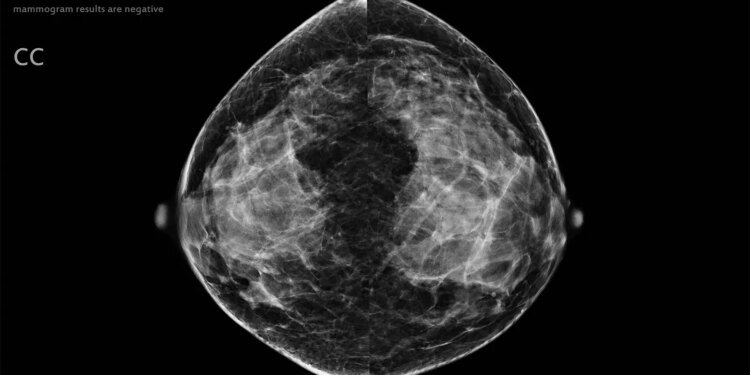

Artificial intelligence (AI) could potentially be used to safely exclude low-risk mammograms from radiologist review, according to results from a prospective noninferiority trial.

The objective of this study was to prospectively confirm that an AI system can be used to completely omit human reading in a large proportion of screening exams classified as low risk for cancer. The study was conducted at a single site in Spain and included 31,301 women (median age 59), 55% of whom underwent digital mammography, and 45% who underwent digital breast tomosynthesis (DBT).